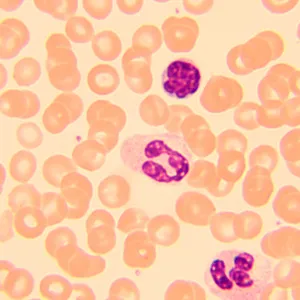

Биологический микроскоп MAGUS Bio 250T – профессиональный прибор для наблюдения биологических образцов в проходящем свете. Основным методом исследований является светлое поле – он доступен в комплектации «из коробки». Методы темного поля, поляризованного света и фазового контраста тоже могут использоваться, но для этого потребуется оснастить микроскоп опциональными аксессуарами. Микроскоп отлично подходит для лабораторных и научно-исследовательских наблюдений в медицине, фармацевтике, криминалистике, сельском хозяйстве и других областях науки.